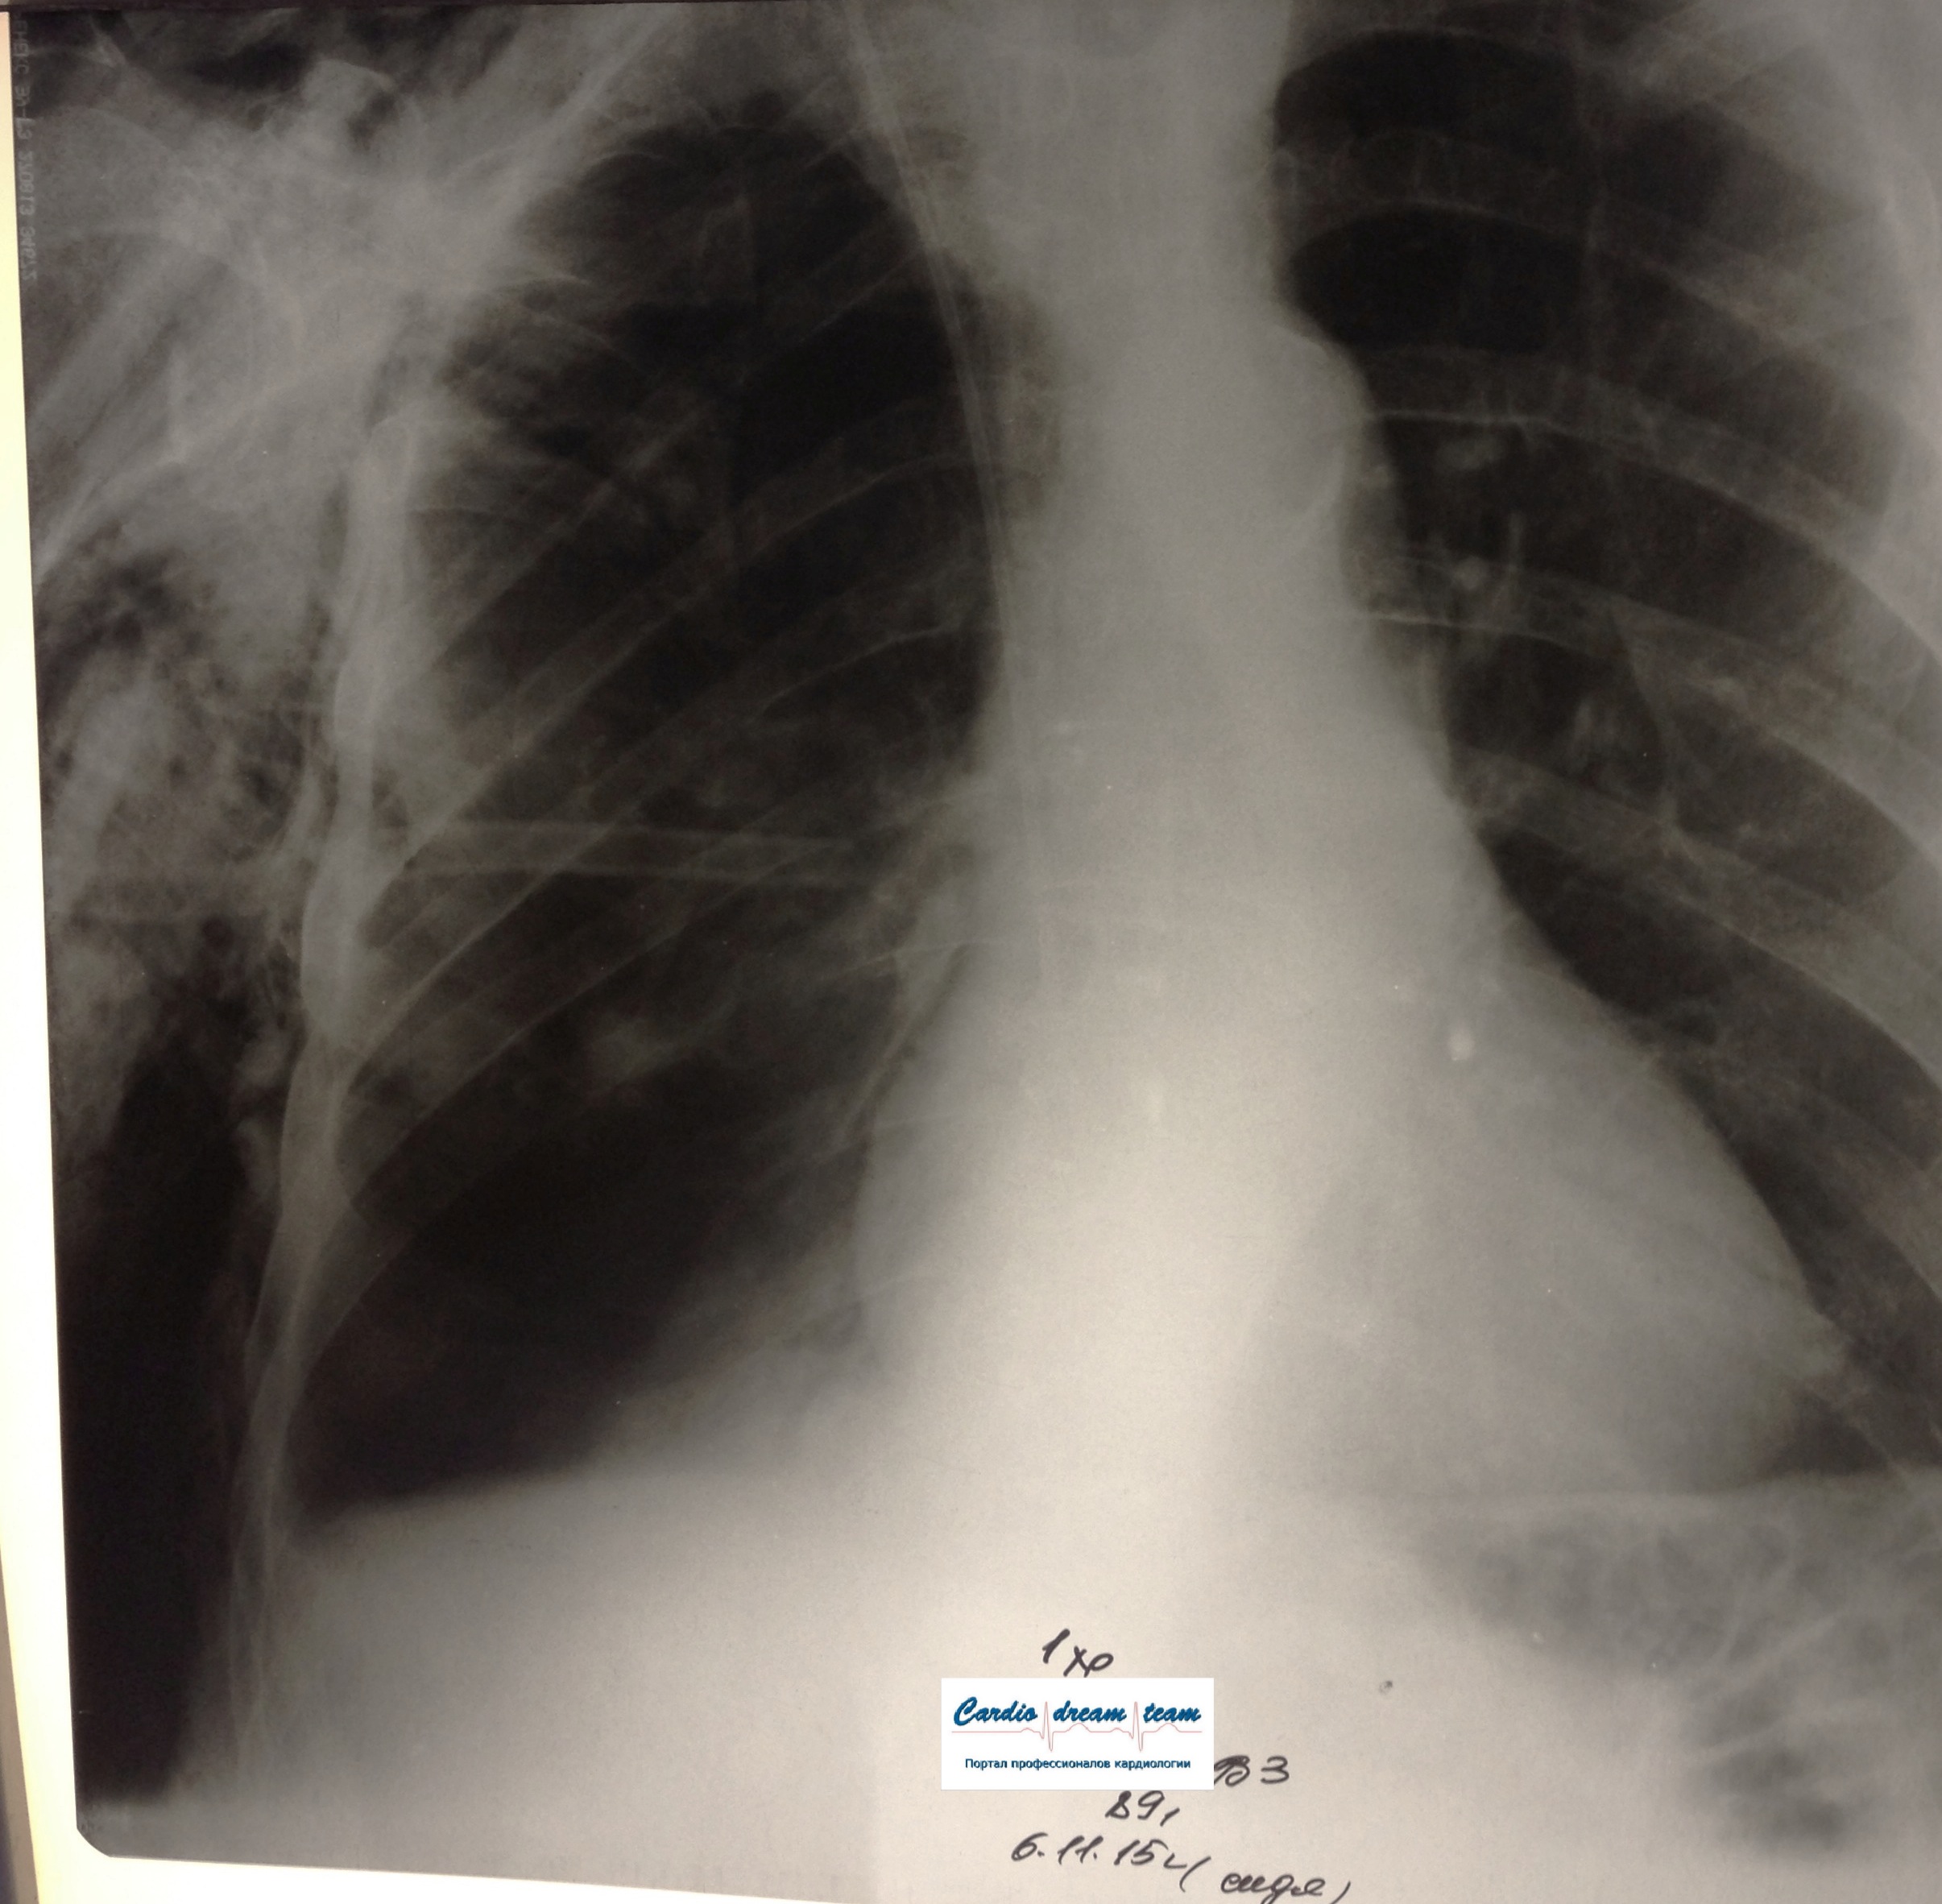

ИССЛЕДОВАНИЕ ОРГАНОВ ГРУДНОЙ КЛЕТКИ Дата 01-ОКТ-15 время 11.30 ОПИСАНИЕ: Проведена рентгенография органов грудной клетки в прямой проекции, положение сидя, условия ПИТ, Р-контроль Легочные поля: Справа легкое расправлено не полностью, апикально до 3го ребра прослеживается свободный газ в плевральной полости. Тень дренажа справа. Тень подключичного катетера в проекции ВПВ. Легочный рисунок: сгущен справа в прикорневой зоне, диффузно деформирован Корни: малоструктурны, обогащены Синусы: нечеткие Сердце: широко лежит на диафрагме (позиционно) ЗАКЛЮЧЕНИЕ: Течение правостороннего пневмоторакса, положительная Р-динамика. Состояние дренирования правой плевральной полости. Р-признаки полнокровия сосудов МКК. Пневмосклероз. Р-контроль .────────────────────────────────────────────────────────────────────── ИССЛЕДОВАНИЕ ОРГАНОВ ГРУДНОЙ КЛЕТКИ Дата 02-ОКТ-15 время 1015 ОПИСАНИЕ: